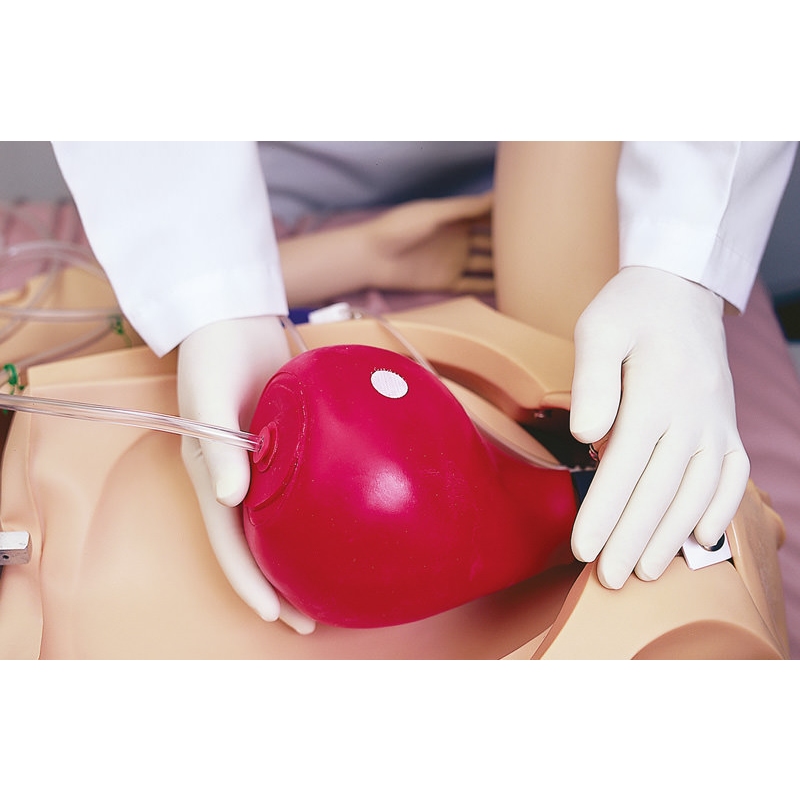

Noelle Simulator poroda mater in novorojenčkov

Zasnovan tako, da zagotavlja popolno porodno izkušnjo pred, med in po porodu.

- več lokacij posteljice

- zamenljivi dilatacijski pripomočki